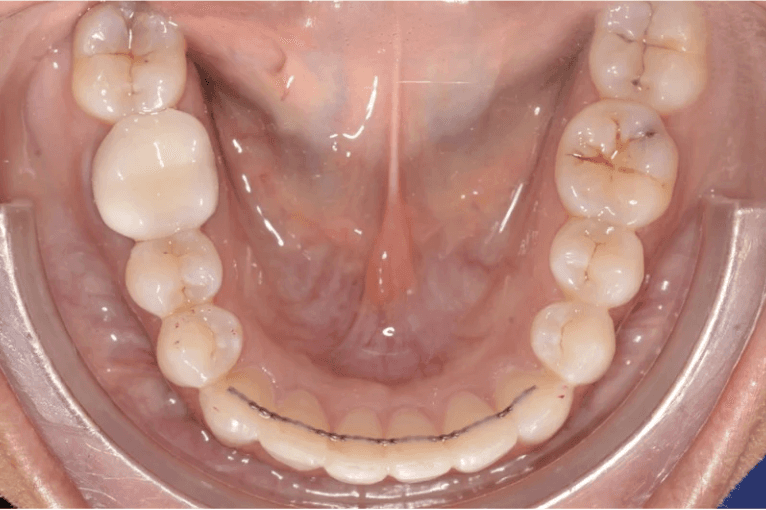

Diagnosis: Lower anterior crowding, LL3 crossbite, deep bite, missing UL6.

Final results

INTRAORAL